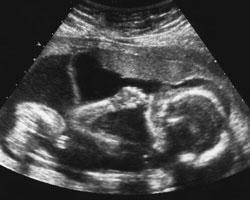

Ecografia das 19 semanas

Entre as semanas 19 e 20 de gravidez, poderás fazer a ecografia morfológica, que serve para avaliar a estrutura e biometria fetal, bem como para diagnosticar anomalias no desenvolvimento fetal. No caso de se diagnosticar uma malformação incompatível com a vida, está contemplada a possibilidade de interromper a gravidez até à 22ª semana. Nesta ecografia também costuma ver-se claramente o sexo do bebé.